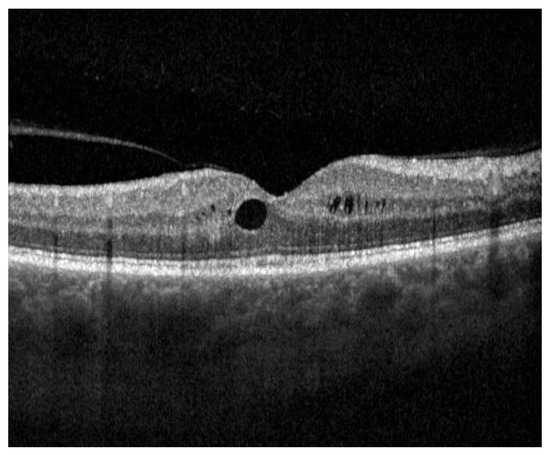

Figure 6.

Pseudophakic cystoid macula edema (PCME), identified by the dark areas representing intraretinal fluid, occurring 4 weeks after cataract surgery imaged with spectral-domain optical coherence tomography (SD-OCT). Vitreous body detachment can accessorily be seen on the left side of the image.